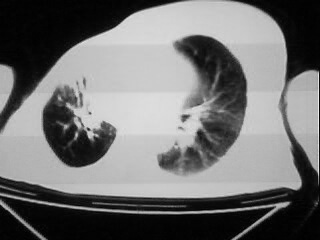

以下是引用随光逐影在2009-2-10 0:07:00的发言:[br]1)右肺放射性肺炎并节段性肺不张?请结合相关病史。2)右侧胸膜肥厚、粘连。3)心包膜增厚(或心包少量积液)。